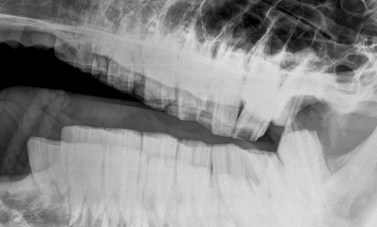

image image image

Fig. 13.43 Radiograph (A) and CT images (B and C) of a compound odontoma in a 2-year-old TB colt.

(Images courtesy of J. Easley.)